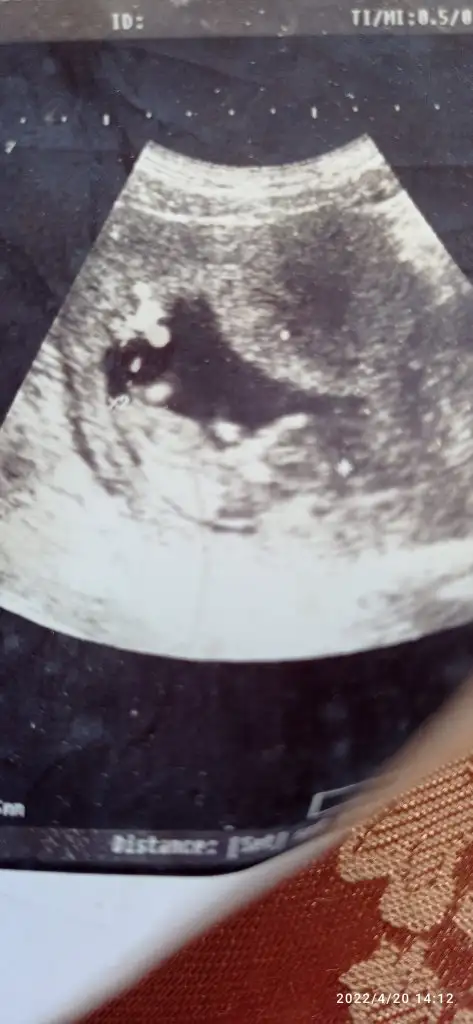

Selam kızlar, vajinal USG ile bakıldı sizce cinsiyet nedir 6+3.